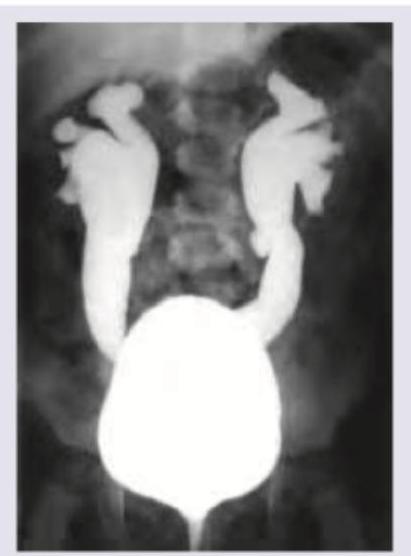

Identify the grade of vesico-ureteric reflux in the picture below?

Explanation: ***Grade V*** - This image shows **severe dilation** and **tortuosity of the ureter**, along with **blunting of the renal calyces** and loss of papillary impressions, extending all the way to the renal pelvis. - Grade V VUR indicates the most severe form of reflux, with significant distortion of the pelvicalyceal system, often associated with **renal parenchymal damage**. *Grade II* - Grade II VUR involves reflux into the **ureter, renal pelvis, and calyces**, but with **no dilation** and normal calyces. - The image clearly displays significant dilation and blunting of calyces, which is beyond Grade II. *Grade III* - In Grade III VUR, there is reflux into the **ureter** and **pelvicalyceal system (renal pelvis and calyces)** with **mild to moderate dilation** and slight blunting of the calyces. - The marked tortuosity and severe dilation seen in the image exceed the characteristics of Grade III. *Grade IV* - Grade IV VUR is characterized by **moderate to severe dilation** and **tortuosity of the ureter** and pelvicalyceal system, with **moderate blunting** of the calyces. - While there is severe dilation and tortuosity, the extent of calycial blunting and loss of papillary impressions in the image is more consistent with Grade V.